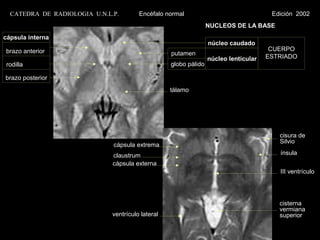

CATEDRA DE RADIOLOGIA U.N.L.P.        Encéfalo normal                                Edición 2002

NUCLEOS DE LA BASE

cápsula interna

núcleo caudado

brazo anterior                                                                         CUERPO

putamen                            ESTRIADO

núcleo lenticular

rodilla                                            globo pálido

brazo posterior

tálamo

cisura de

Silvio

cápsula extrema

claustrum                                                  ínsula

cápsula externa

III ventrículo

cisterna

vermiana

ventrículo lateral                                         superior